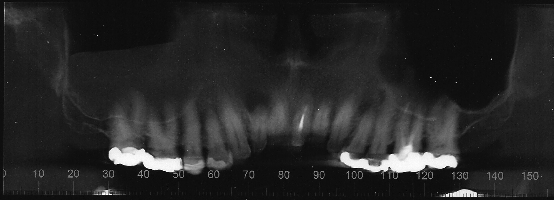

Tomografia Arcada Superior

ImgArcadaDentaria.png